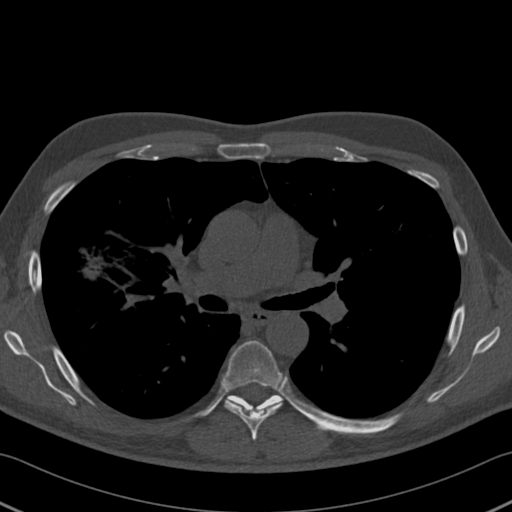

Choose if image shown above is Real or Fake :

Real

Fake